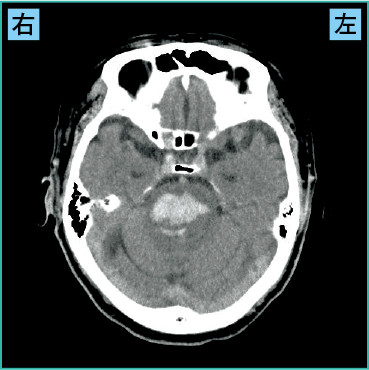

4)脳幹出血の画像の見方

図6-1は脳幹出血の画像です。脳幹は中脳・橋・延髄から構成されますが、脳幹出血で多いのは橋出血です。

図6-1 脳幹出血(CT)

責任血管は脳底動脈から分岐する橋動脈です。

橋は意識や呼吸の調整などの役割があるため、障害されると強い意識障害や呼吸障害を起こし、脳出血のなかで最も予後不良です。

図6-1の症例では出血量が多く、強い意識障害と呼吸障害などが出現していました。

また、橋には左右の運動を司る錐体路が通るため、四肢麻痺の症状が起こったり、嚥下中枢も隣接することから嚥下障害が出ることもあり(図4参照)、救命できたとしても大きな後遺症が残ります。